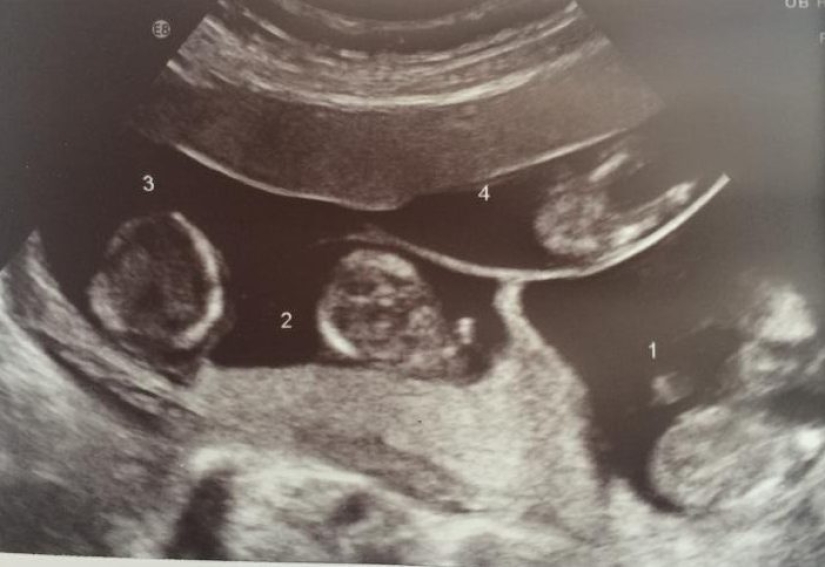

The woman could not get pregnant for a long time due to health problems, but in 2014 the test showed a long-awaited positive result. What was the surprise of the newly minted parents and doctors when it was discovered that they were expecting not one child, but four at once!

Quadruplets conceived without artificial insemination are born once per 700,000. In the UK, this case is unique. Katelina conceived four fraternal twins at the same time, which are not similar to each other. Now the children have already turned 4 years old.